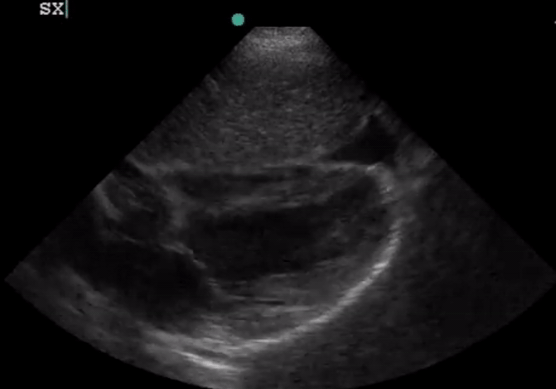

Large pericardial effusion with evidence of RV free wall collapse. PSL view.

Subxiphoid

• Highest complication rate

• Potential structures to be damages: liver, lung, IVC, internal thoracic artery, left anterior descending aorta, colon and stomach

• Longest distance from skin to pericardial fluid

Subxiphoid approach. Insert needle (not in plane) between xiphoid and left costal margin. Aim to left shoulder.